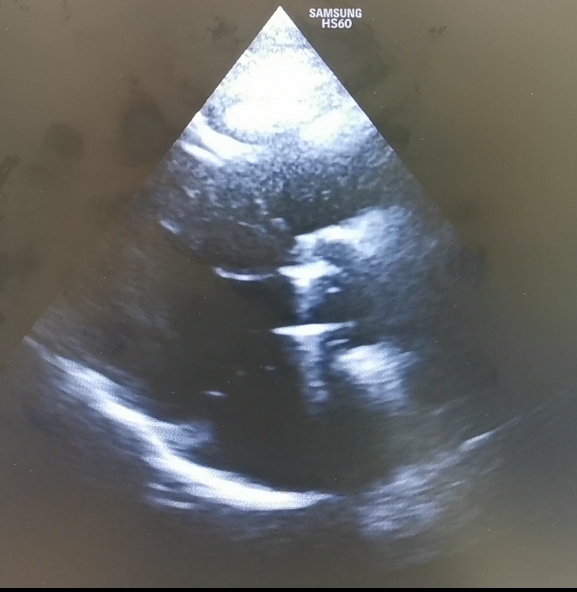

Imaginea atasata este preluata din ghidul european de valvulopatii 2021.